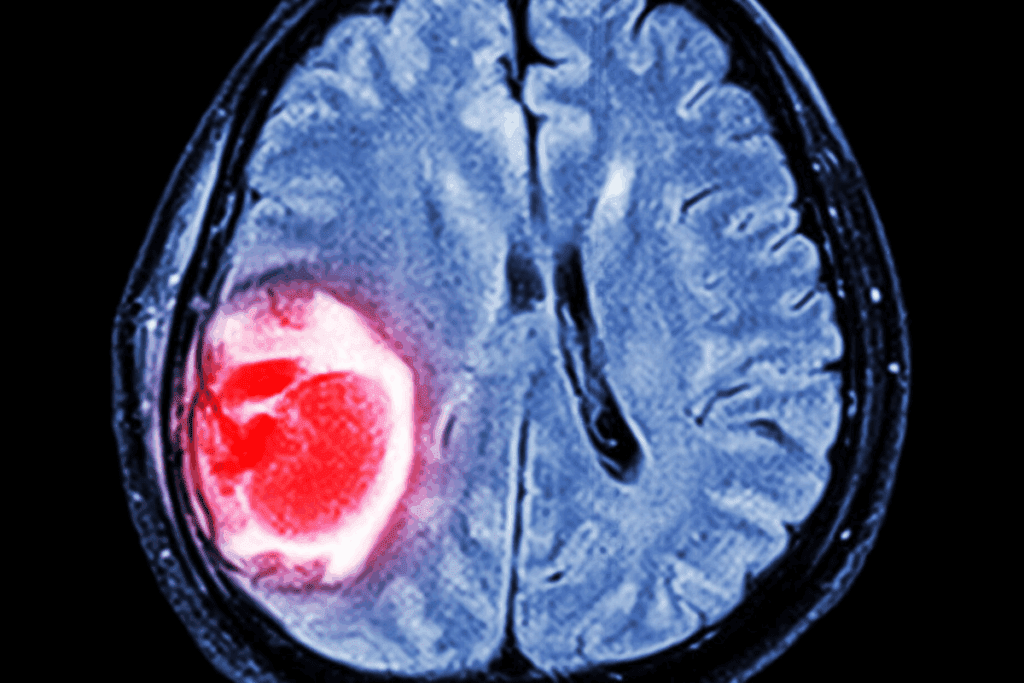

Before, finding brain tumors meant using invasive methods like biopsies. We also used MRI and CT scans. Now, researchers think blood tests could find biomarkers and genetic changes linked to glioma and other brain cancers.

Imaging Techniques

Magnetic Resonance Imaging (MRI): MRI is the best for seeing brain tumors. It shows soft tissues well and tells where the tumor is.

Computed Tomography (CT) Scan: CT scans use X-rays to see the brain. They’re good in emergencies or when MRI isn’t available. But they don’t show soft tissues as well as MRI.